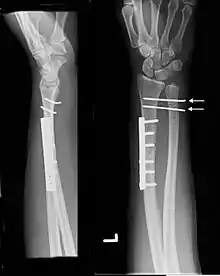

Galeazzi fracture

The Galeazzi fracture is a fracture of the distal third of the radius with dislocation of the distal radioulnar joint. It classically involves an isolated fracture of the junction of the distal third and middle third of the radius with associated subluxation or dislocation of the distal radio-ulnar joint; the injury disrupts the forearm axis joint.[1]

| Galeazzi fracture. Arrow points at the dislocated ulnar head | |